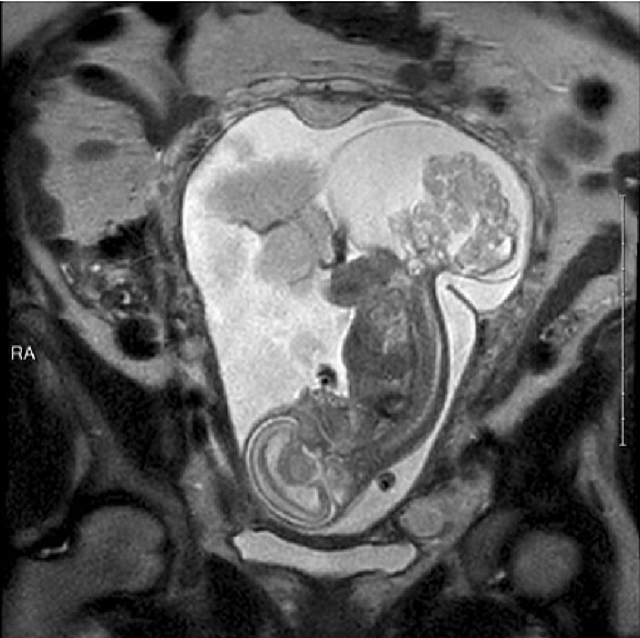

Το ιεροκοκκυγικό τεράτωμα είναι ένας όγκος που μεγαλώνει στην περιοχή του ιερού οστού και του κόκκυγα – ένα σπάνιο σενάριο που παρουσιάζεται σε 1 στις 35.000 γεννήσεις. Στο σύνδρομο αυτό ο αναπτυσσόμενος όγκος «κλέβει» από την αιματική ροή τόσο ώστε σταδιακά προκαλείται καρδιακή ανεπάρκεια – και, άρα, εμβρυϊκός θάνατος.

ιεροκοκκυγικό τεράτωμα

Η Boemer ήταν 23 εβδομάδων και 5 ημερών όταν εισήχθη εσπευσμένα στο χειρουργείο. Τη στιγμή εκείνη, ο όγκος ήταν λίγο μεγαλύτερος σε μέγεθος από το ίδιο το έμβρυο.